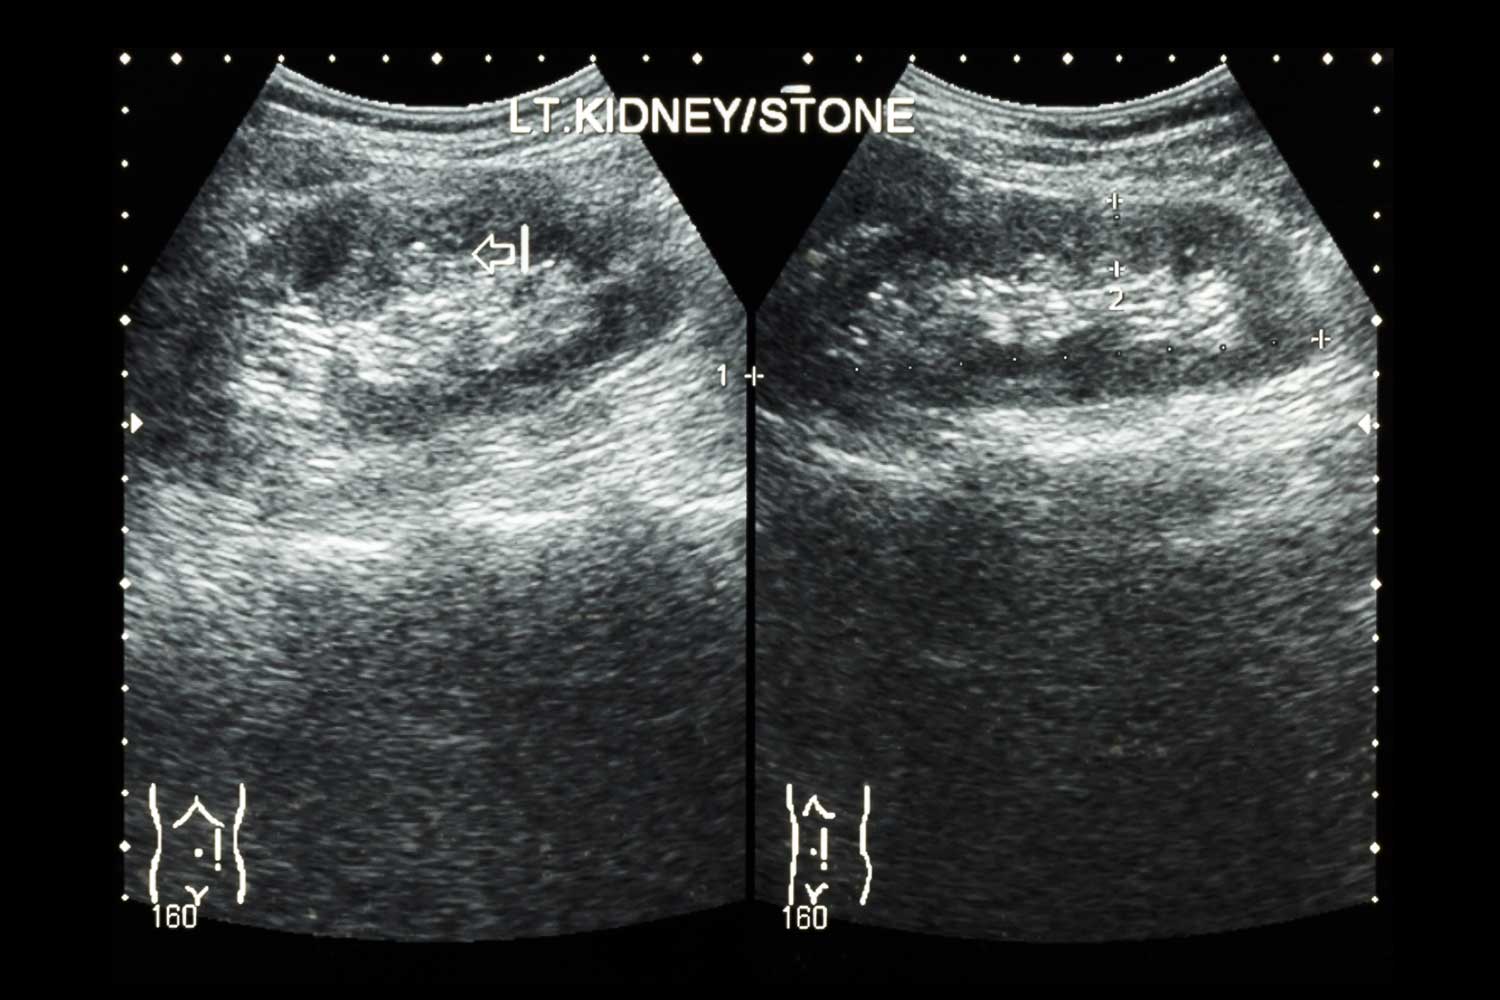

- Kidney stones — while CT is the gold standard for stone detection, ultrasound can identify many stones (especially larger ones) without radiation exposure and is often used as the first test in children, pregnant women, and patients who need to limit radiation

A kidney ultrasound — also called a renal ultrasound — uses sound waves to create real-time images of the kidneys, ureters (the tubes that connect the kidneys to the bladder), and bladder. It shows the size, shape, position, and internal structure of each kidney, including the cortex (outer tissue), medulla (inner tissue), collecting system (where urine collects), and the surrounding fat and tissue.